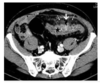

Dg ?

Diverticulite compliquée d’une perforation.

Scanner au temps portal après injection de produit de contraste iodé. La paroi du côlon sigmoïde est très épaissie (étoile). Il existe une infiltration de la graisse périsigmoïdienne en avant de celui-ci (flèches fines). La présence d’air en dehors du tube digestif (flèche) traduit la perforation de ce dernier.